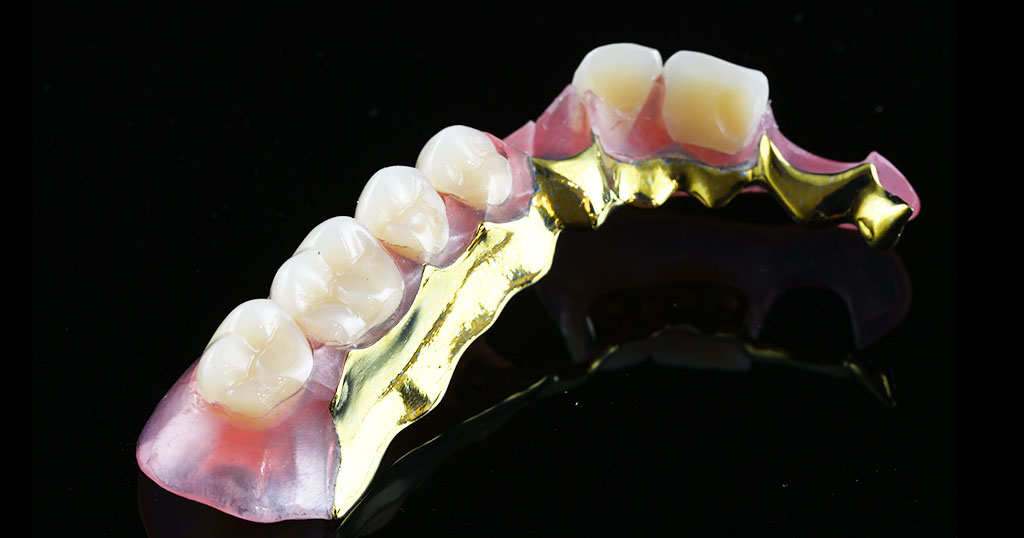

セットしたコンティース

上顎右124567番の欠損を補うコンティース(部分入れ歯)

金属部分がない、フィット感がある、入れ歯を支える歯への負担を軽減させるため、上顎右124567番の欠損を補う着脱が簡単なコンティースを作成

80代男性。クラスプの金属が見えないタイプの入れ歯です。コンティース(三和デンタル社製)異物感の少ない、コンタクトレンズのように気軽に取り外せる部分入れ歯です。